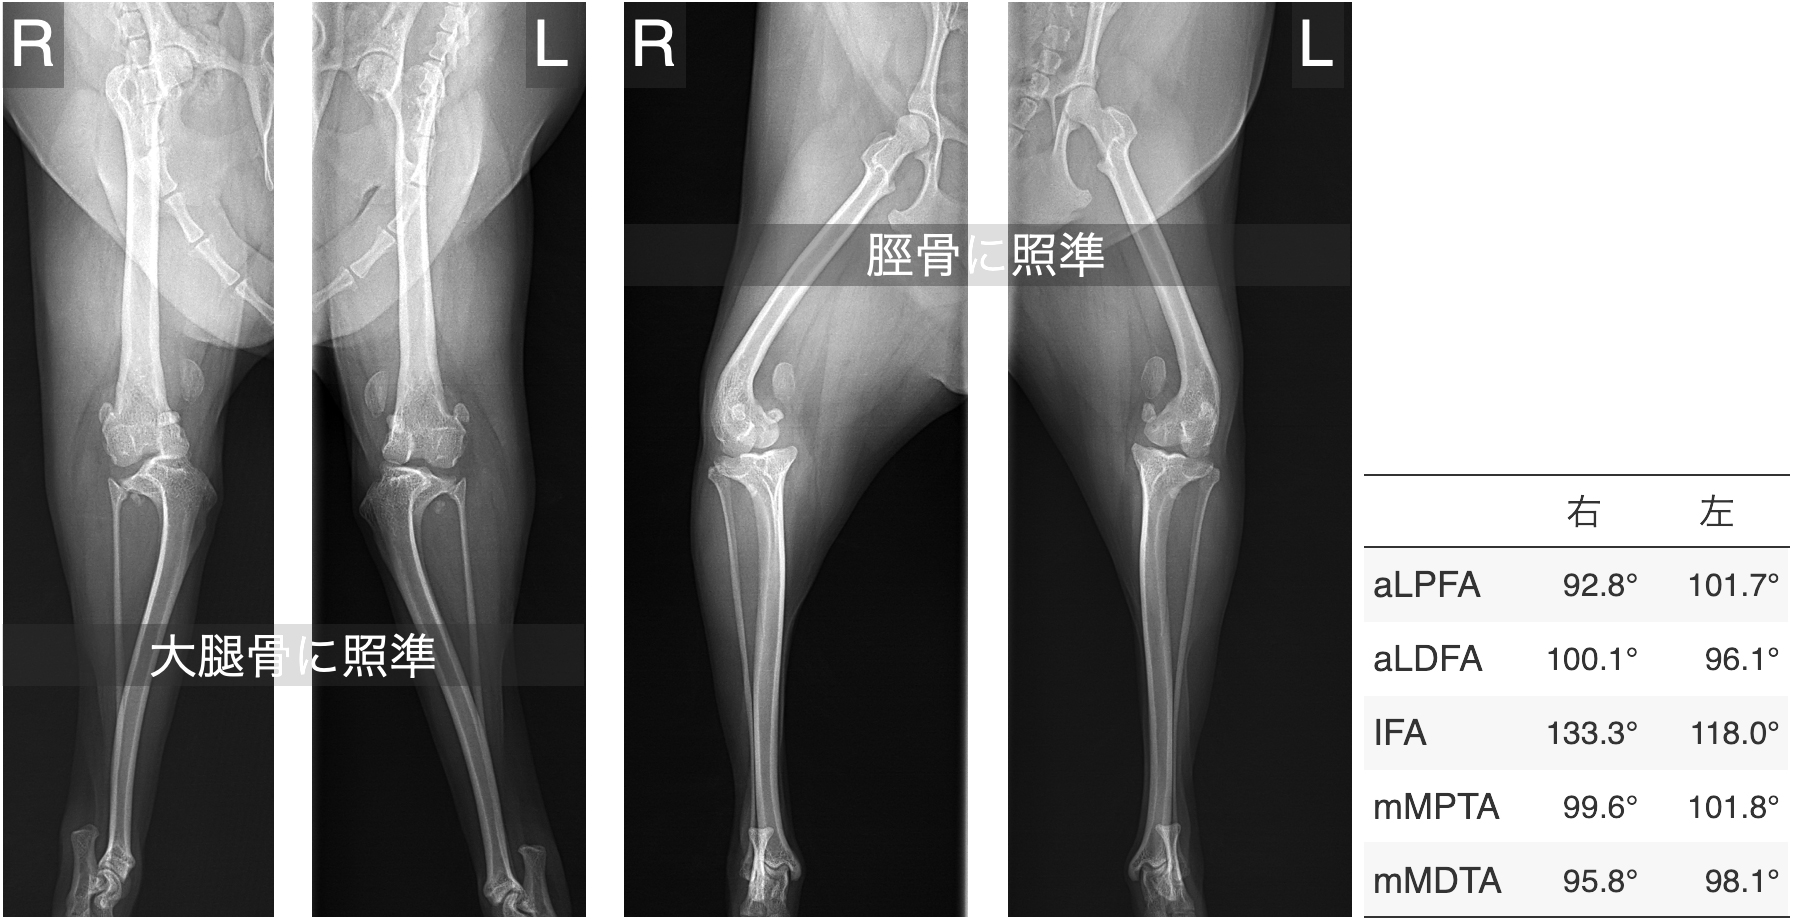

レントゲン検査で骨の変形が疑われる場合には、より詳しい評価のためにCT検査をおすすめしています。

レントゲンでは全体像はつかめても、骨の捩れや傾きといった詳細な情報までは正確に把握できないことがあるからです。

以下は、グレード4の膝蓋骨脱臼でよくみられる骨の変形の一例です。

ただし、骨の変形は症例ごとにその部位や程度が異なるため、CTによる三次元的な形態解析を行うことが、適切な手術計画を立てるうえで重要です。